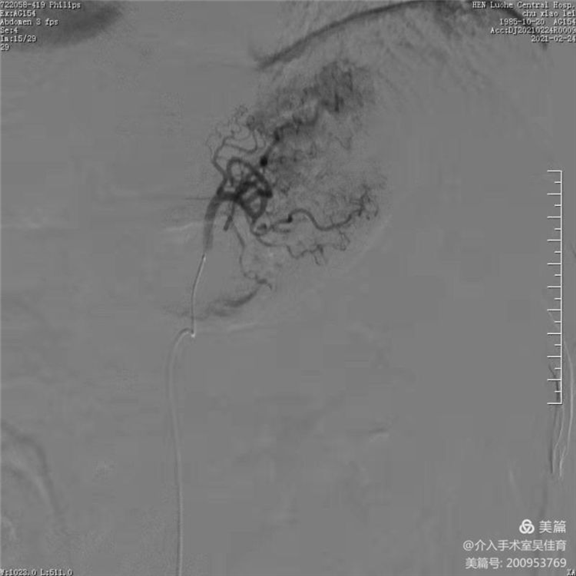

胃左动脉造影显示粗大的胃左动脉,血供丰富